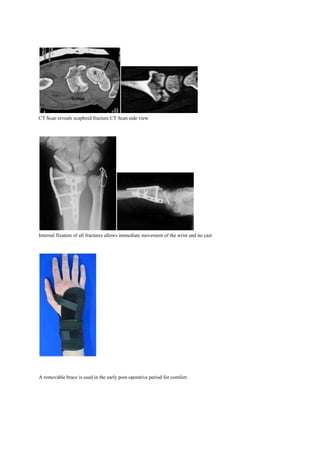

A 27 year old snow boarder falls at high speed. The Xrays tend to understate the injury. There is not only a Colles

fracture with an associated fracture at the base of the ulna styloid but also a Scaphoid fracture. The degree of joint

surface disruption and degree of comminution ( multiple fragments) is best seen on the CT scan.

Front view Xray

Side View Xray

CT Scan reveals scaphoid fracture CT Scan side view

Internal fixation of all fractures allows immediate movement of the wrist and no cast

A removable brace is used in the early post-operative period for comfort.